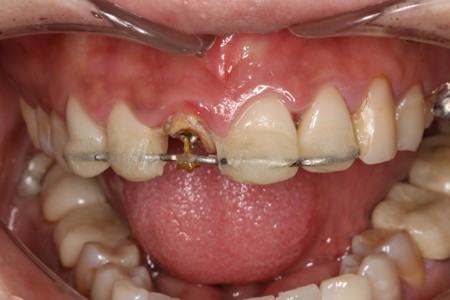

崩壊した虫歯の治療法「エクストリュージョン」

虫歯が進行して歯が大きく崩れてしまうと、削って被せ物を装着するための部分が残らないことがあります。

このような場合、多くのケースで「抜歯」が選択されます。

当院では、そうしたケースでも「エクストリュージョン」という治療法によって、歯を抜かずに残せる可能性があります。

エクストリュージョンは矯正治療の一種で、歯ぐきの中にある歯の根を少しずつ外に引き出し、被せ物を装着できるスペースを確保する治療です。歯を残せる可能性を広げながら、噛む機能や見た目にも配慮した治療を行います。